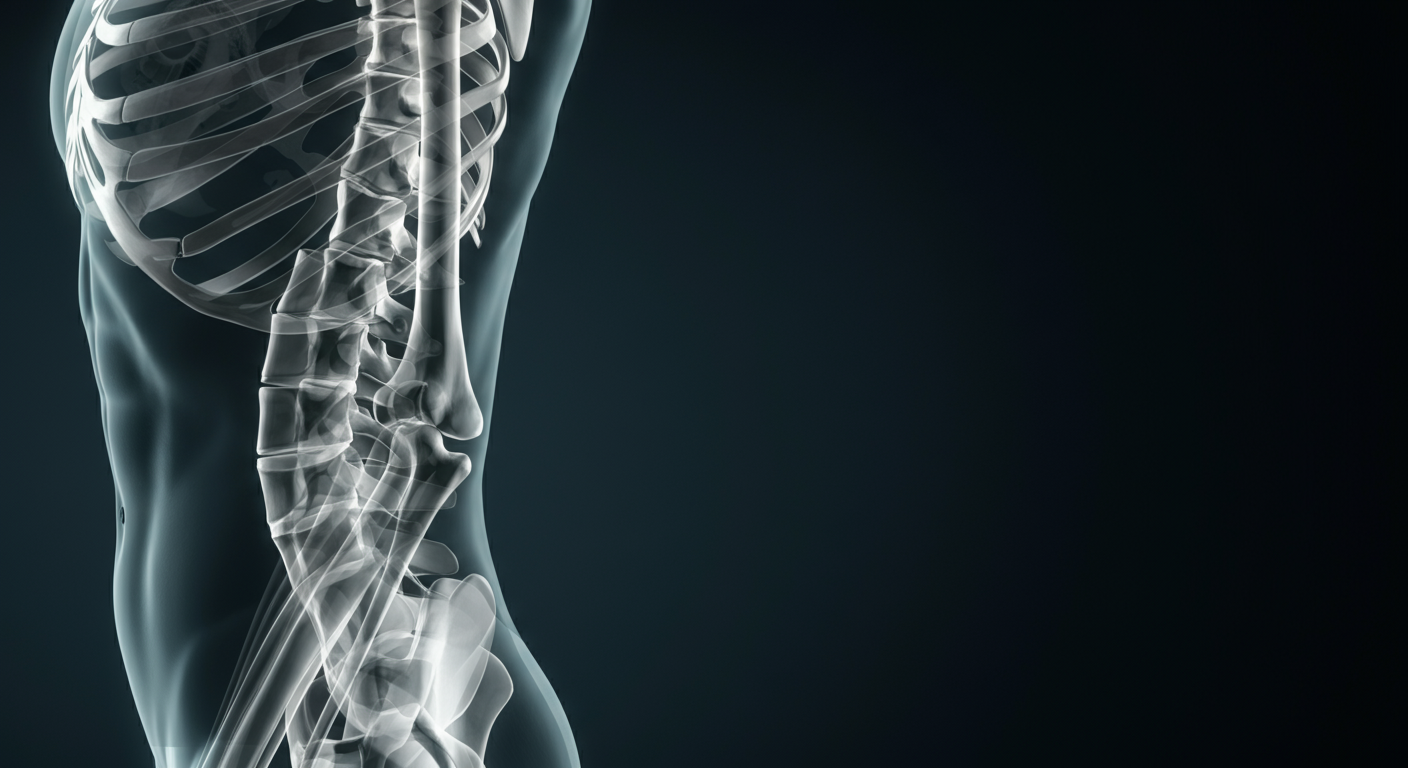

The traditional medical advice to “rest and protect” joints affected by osteoarthritis (OA) is not just outdated—it is biologically counterproductive. New clinical data indicates that cartilage is a dynamic, mechanosensitive tissue that requires cyclical loading to maintain its structural integrity. The “wear and tear” myth is being replaced by a “use it or lose it” reality, where specific types of high-impact exercise, such as running, actually stimulate cartilage repair and reduce systemic inflammation. The most significant shift in the next 12 months will be the integration of aggressive joint-loading protocols with the rapid weight loss seen in the GLP-1 drug era, creating a new standard of “metabolic orthopedics.”

Osteoarthritis has long been treated as a mechanical failure of a biological shock absorber. However, the latest research suggests OA is as much a metabolic disease as it is a mechanical one. The convergence of sport science and metabolic medicine reveals that exercise does more than strengthen the muscles surrounding a joint; it resets the joint’s internal chemistry. By analyzing the latest data on runners and weight-loss interventions, we see a clear pattern: the joint environment thrives under pressure and suffers in stasis.

The prevailing fear that high-impact activities like running accelerate joint degradation is debunked by recent longitudinal data. A 2023 study highlighted that runners do not exhibit higher rates of knee osteoarthritis compared to non-runners. In fact, the mechanical stress of running appears to trigger mechanotransduction—a process where cells convert mechanical stimulus into chemical activity—effectively “feeding” the cartilage by circulating synovial fluid.

This mechanical necessity is now colliding with the rise of GLP-1 medications. While these drugs offer “significant improvement” in joint pain through rapid weight loss, they also risk decreasing bone density and muscle mass. The hidden pattern here is the synergy between pharmacology and physics: the weight loss provided by GLP-1s reduces the “static” load on joints, while high-impact exercise provides the “dynamic” load necessary for cartilage survival. Without the exercise component, GLP-1 patients may find themselves with lighter bodies but more fragile skeletal structures.

The future of OA management is not about avoiding impact; it is about optimizing it. The data is clear: sedentary behavior is a primary driver of cartilage atrophy.

- Cartilage thrives on stress: Cyclical loading (running, jumping) is necessary for nutrient exchange within the joint.